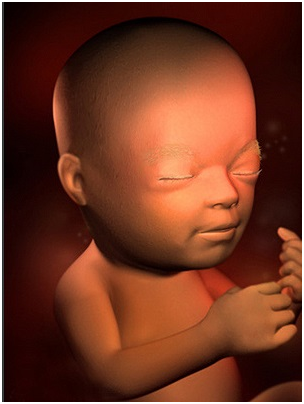

怀孕第28周胎儿图 从现在开始,你就进入了孕晚期,要注意的事情很多呦!你要每天做胎动...

怀孕第28周胎儿图 从现在开始,你就进入了孕晚期,要注意的事情很多呦!你要每天做胎动... -

怀孕第29周现在你能明显地感觉到宝宝的胎动了,如果你注意到胎动有所减少,要让你的医生知道哦!...

怀孕第29周现在你能明显地感觉到宝宝的胎动了,如果你注意到胎动有所减少,要让你的医生知道哦!... -

怀孕第30周你一直在给宝宝讲故事、唱歌吗?如果是的,那么现在的宝宝已经非常熟悉你的声音了!这...

怀孕第30周你一直在给宝宝讲故事、唱歌吗?如果是的,那么现在的宝宝已经非常熟悉你的声音了!这... -

怀孕第31周这周宝宝的眼睛时开时闭,他大概能够看到子宫里的景象了!你可能时常会感到呼吸越发困...

怀孕第31周这周宝宝的眼睛时开时闭,他大概能够看到子宫里的景象了!你可能时常会感到呼吸越发困... -